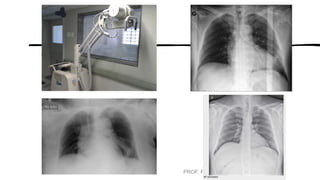

POSICIONAMENTOS DE ROTINA ESPECIAIS

PARA TÓRAX

• AP em decúbito dorsal ou reclinado (semiereta)

• Decúbito lateral

• Apicolordótica

• Oblíqua anterior e posterior